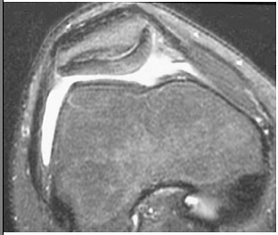

| MRI demonstrates cartilage abnormality in the patella of a cyclist. Courtesy of Duke University Medical Center, Musculoskeletal Division, Durham, NC. |

Overall, the most common problem is patellofemoral disease, which accounts for as much as 25% of all cycling injuries, according to experts.

"The overwhelming presenting injury these cyclists have is patellofemoral disease -- chondromalacia or cartilage issues in the patellofemoral joint," said Dr. Nancy Major, associate professor of radiology at Duke University in Durham, NC. "Even the tendon can get something called ‘jumper’s knee,’ which is commonly seen in basketball players."